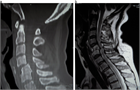

1. 頚髄症と腰部脊柱管狭窄症合併例では、頚椎手術を優先するが、腰部脊柱管狭窄症が主訴となっている場合には頚椎が伸展しないように術中体位に十分注意する。